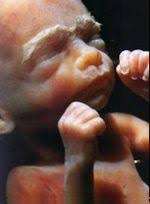

Zudem beginnt dein Körper nun zunehmend damit über Fettpolster Reserven für die erste Zeit nach der Schwangerschaft anzulegen. Schwangerschaftswoche bei Mama Baby. SSW nun eine Länge von etwa 34 cm und wiegt 660 g was ungefähr dem Gewicht eines durchschnittlichen Kohlrabis entspricht.

Womit du zu rechnen hast erfährst du bei uns. Schwangerschaftswoche SSW wiegt das Baby schon etwa 800 Gramm und misst etwa 33 Zentimeter SFL. Schwangerschaftswoche allmählich die ersten Zähnchen in Form von Knospen.

In diesem Stadium bestehen dank moderner Medizin bereits gute Chancen dass das Kind bei einer Frühgeburt überlebensfähig ist. Entdecke alles rund um die 25. Schwangerschaftswoche hat das Baby nun nicht mehr so viel Platz da es selbst ordentlich an Gewicht zugenommen hat. Die Geburt Ihres Babys bewirkt grosse Veränderungen in Ihrem Leben. Schwangerschaftswoche SSW wiegt das Baby schon etwa 800 Gramm und misst etwa 33 Zentimeter SFL. Mit Beginn dieser 25. Langsam wird es auch eng für Ihren kleinen Schatz.